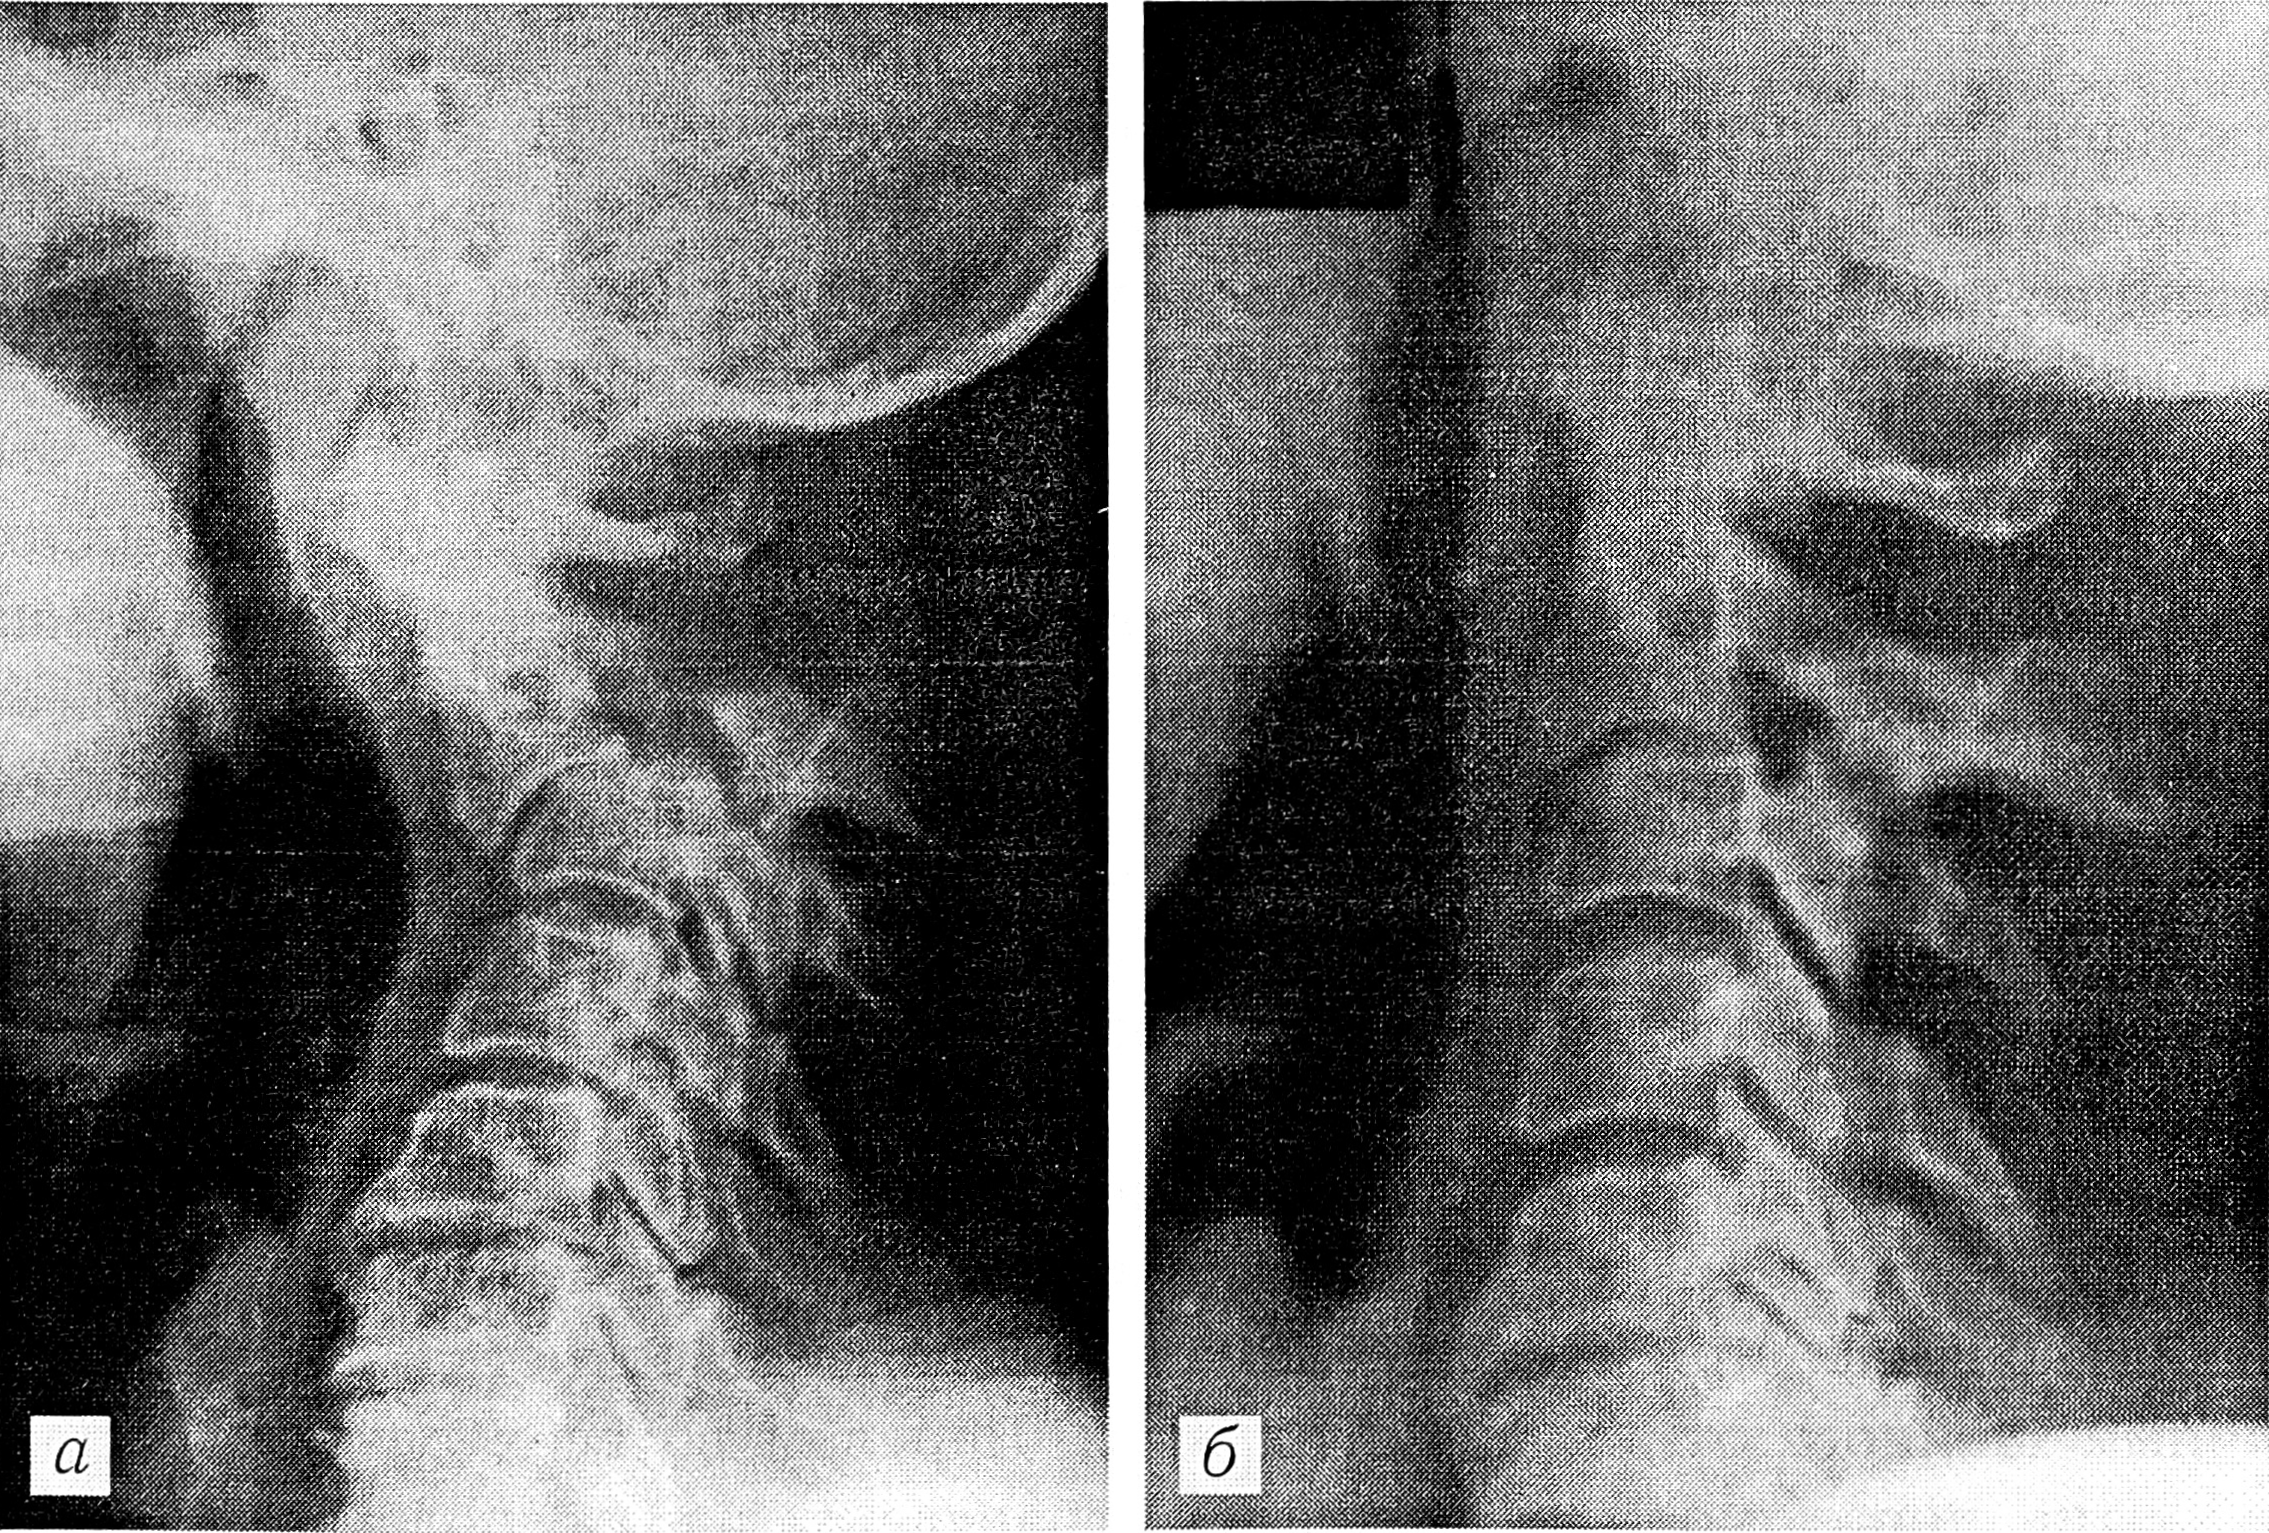

Произведены рентгенография и компьютерная томография, диагностирован перелом Джефферсона (рис. 2, а). Наложен гало-аппарат, в котором достигнута репозиция отломков (рис. 2, б). Аппарат снят через 3 мес. При рентгенографии и компьютерной томографии констатирована консолидация перелома.

Рис. 2. Рентгенограммы больной Г.

а — на снимке, сделанном через рот, определяется перелом Джефферсона, видно расхождение боковых масс атланта, суставные щели боковых атлантоаксиальных суставов не дифференцируются; б — за счет тракции в гало-аппарате достигнута репозиция отломков: расхождение боковых масс атланта уменьшилось, хорошо определяются боковые атлантоаксиальные суставы.